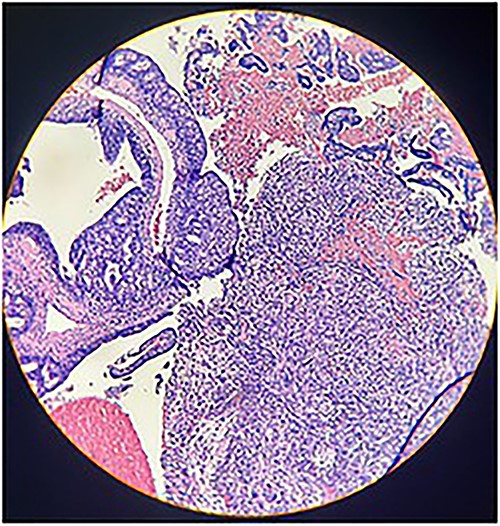

Macroscopically, an amorphous uterus weighing 397 g and measuring 12 × 9 × 7.5 cm with a brown serosa, and multinodular violaceous areas was examined. When incised, the endometrial cavity was occupied by a whitish polypoid mass of 8 × 5 cm which invaded the myometrium. In addition, multiple firm whitish nodules ~2 × 1.5 cm in diameter were identified. Bilateral ovaries and fallopian tubes appeared to be of normal morphology and size. Histologically, there was evidence of epithelial and sarcomatous components (Figs 1 and 2), and the epithelial component developed atypical glands (Fig. 3). The diagnosis of MMMT was given due to histologic findings.

Photomicrograph shows epithelial components that form atypical glands and solid nodules with a sarcomatous component (H & E stain ×10).